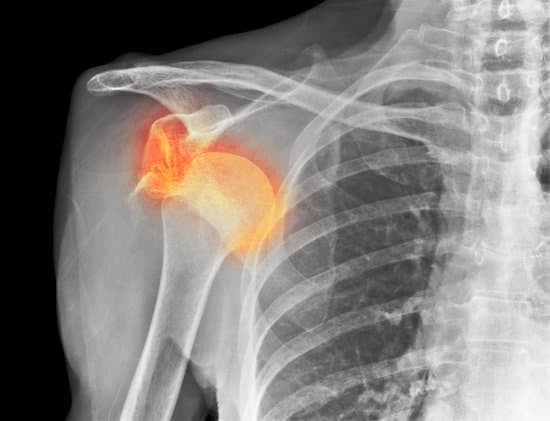

견관절 탈구 (Shoulder Dislocation): 원인, 증상 및 치료

견관절 탈구(Shoulder Dislocation)는 어깨 관절의 상완골(팔뼈)이 관절을 둘러싼 견갑골(어깨뼈)의 관절와(glenoid)에서 벗어나는 상태를 말합니다.

X-ray 촬영

탈구된 상완골의 위치를 확인하고 뼈에 손상이 있는지 평가합니다.